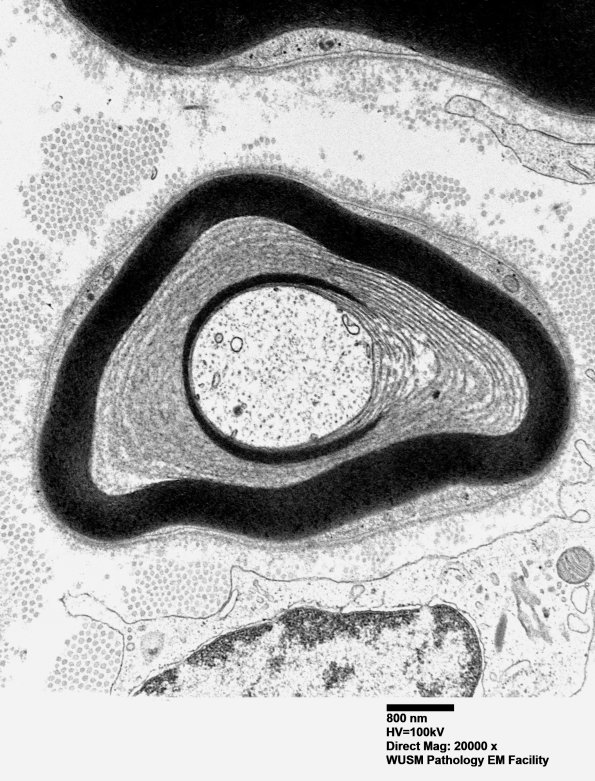

Additional examples of POEMS lesions in this patient. (electron micrograph)